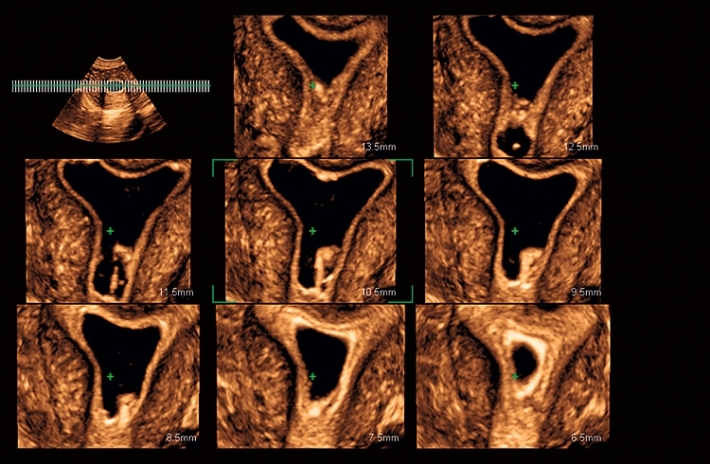

Изображения